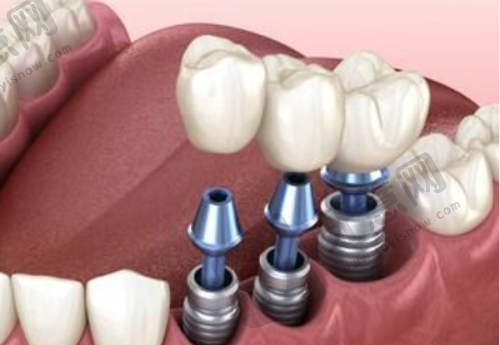

科室设置丰富。北京欢乐英辰口腔门诊部成立于20XX年,经过多年发展,已拥有一定规模,门诊部面积达XXX平方米,诊室内环境舒适、整洁,为患者营造了良好的就医氛围。该门诊部科室设置较为齐全,设有口腔正畸科,专精的正畸医生能够根据患者的不同牙齿情况,制定个性化的正畸方案,帮助患者拥有整齐美观的牙齿;口腔种植科,采用精良的种植技术和优质的种植体材料,为缺牙患者提供稳固、耐用的种植牙修复;还有口腔内科、口腔外科等科室,能够全方面满足患者的口腔治疗需求。

特色项目众多。北京欢乐英辰口腔门诊部拥有多个特色项目。在牙齿正畸项目方面,采用精良的隐形正畸技术,这种技术使用的隐形牙套几乎完全隐形,不影响患者的美观和社交,而且牙套可以自行摘戴,方便患者清洁口腔,减少了牙齿脱矿、龋坏等问题的发生。同时,医生会根据患者的牙齿移动情况,精细调整牙套的力度和方向,确保正畸成效更加理想。种植牙项目,门诊部引进了国内外精良的种植系统,种植过程中,医生凭借不错的技术,能够精细植入种植体,缩短手术时间,减少患者的痛苦。种植体与牙槽骨的结合紧密,稳定性高,使用寿命长,能够为患者修复良好的咀嚼功能。牙齿美白项目,采用安心有效的美白技术,美白剂对牙齿的刺激性小,能够在短时间内让牙齿变得洁白亮丽,而且美白成效持久,让患者拥有自信的笑容。